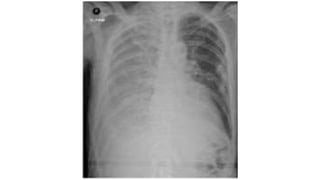

PREVIOUS CXR • PreviousCXRS your best friend. You see a real or possible abnormality on the CXR. • Was it there before? Has it got larger or smaller? Is it unchanged? • A previous CXR will often highlight an important but subtle change. • On the other hand it will frequently provide reassurance that all is well.